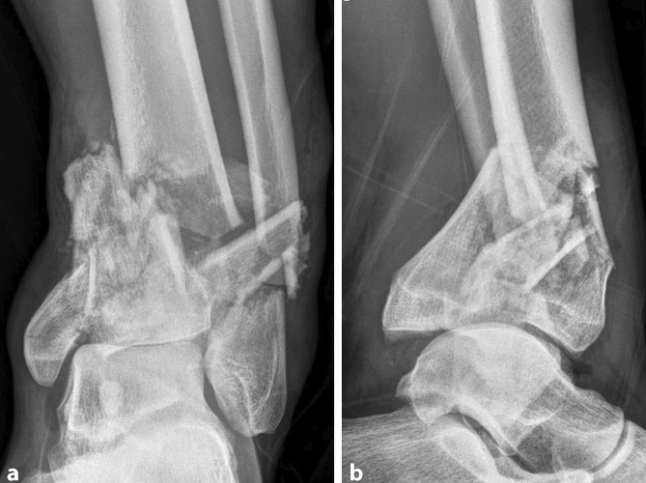

恢复外踝长度与解剖位置,放置解剖钢板。距骨常向前上方移位,将其下压使其软骨面与外踝内侧平齐;以胫腓骨、距骨正常“奔驰三角”为参照,复位钳维持复位。用2.0mm克氏针临时固定外踝与距骨(避开钢板),以距骨为模板重建胫骨远端关节面。

踝内侧作2个辅助小切口,自远端切口,巾钳复位移位的内踝,评估内踝内侧关节面与距骨顶的匹配程度,克氏针临时固定后,采用预弯重建钢板固定。最远端螺钉斜向下45°角置入,上方2枚螺钉斜向上45°角置入。

遵循“由后向前、由外向内”的原则,以距骨关节面为模板复位,克氏针临时固定后,采用踝前方L型钢板固定。依据骨折粉碎程度及钢板固定情况,绝对是否移除克氏针。